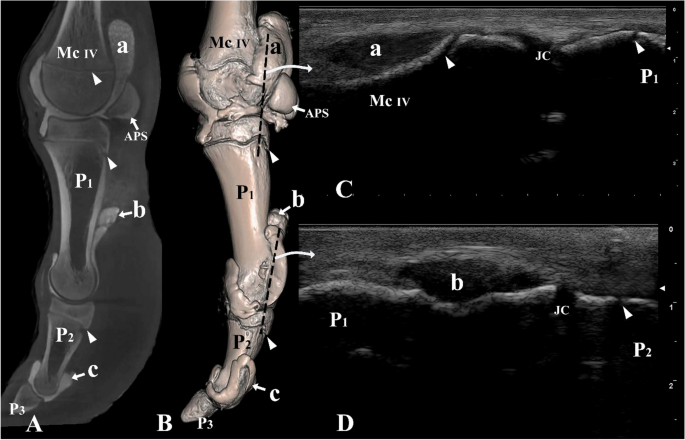

Lateral view of the left digit IV. (A) Sagittal plane CT image; (B) three-dimensional reconstruction (the black dotted line indicating the placement of the ultrasound probe), (C) longitudinal lateral ultrasound image of the metacarpophalangeal joint, and (D) longitudinal lateral ultrasound image of the proximal interphalangeal joint. Mc IV distal end of metacarpal bone IV, P1 proximal phalanx, P2 middle phalanx, P3 distal phalanx, APS abaxial proximal sesamoid bone, a proximal palmar pouch of the metacarpophalangeal joint, b proximal palmar pouch of the proximal interphalangeal joint, c proximal palmar pouch of the distal interphalangeal joint, JC joint cavity. White arrowheads indicate the epiphyseal lines.

The ultrasonographic images revealed that the tendons and other soft tissues surrounding the joint cavities appeared hyperechoic. In contrast, the synovial fluid within the joint cavities demonstrated hypoechoic characteristics. The digit joints were examined with ultrasonography from a dorsal, lateral, and palmar/plantar aspect, in an extended position (Figs. 3C, 5C–E, 6C,D, 7C). The epiphyseal lines of the distal ends of the metacarpal and metatarsal bones and the proximal ends of P1 and P2 were distinguished (Figs. 3C, 5C,D, 6C,D). Furthermore, the joint cavities of the metacarpophalangeal, metatarsophalangeal, proximal interphalangeal, and distal interphalangeal joints were identified via the dorsal aspect (Fig. 5C–E). P3 could not be viewed via the dorsal aspect because of the obstruction of the hoof capsule.

On the lateral aspect of the digit, our observations included the distal end of the metacarpal/metatarsal bones, the metacarpophalangeal/metatarsophalangeal joint cavities, P1, proximal interphalangeal joint cavities, and P2 (Fig. 6C,D). Furthermore, the large palmar/plantar pouches of the metacarpophalangeal/metatarsophalangeal and proximal interphalangeal joints were identified (Fig. 6C,D).

Computed tomography

The CT scans in this study provided three-dimensional images with exceptional detail, allowing for a clear visualization of the distal limb including joint cavities, recesses, and pouches of the metacarpophalangeal/metatarsophalangeal joints, as well as the proximal and distal interphalangeal joints (Figs. 3A,B, 5A,B, 6A,B, 7A,B). The CT results were in accordance with the ultrasound findings, supporting the accuracy of our anatomical observations.